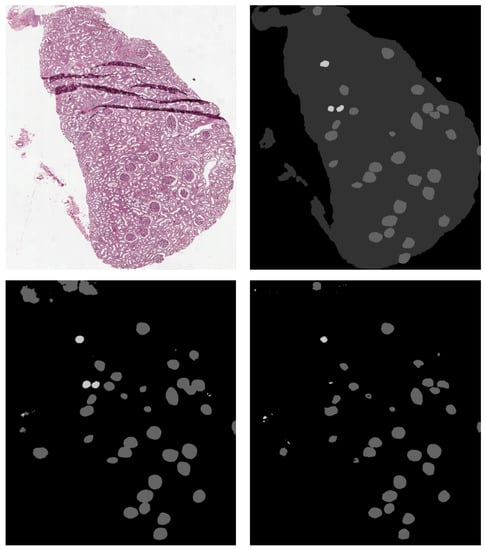

The best results on non-sclerotic glomeruli have been obtained using DeepLab v3+, while for sclerotic glomeruli the best model was SegNet. An example of the output of our semantic segmentation framework is depicted in Figure 9.

Figure 9. Top Left: original image. Top Right: ground truth. Bottom Left: SegNet prediction. Bottom Right: DeepLab v3+ prediction. Sclerotic glomeruli and non-sclerotic ones are white and gray colored, respectively.